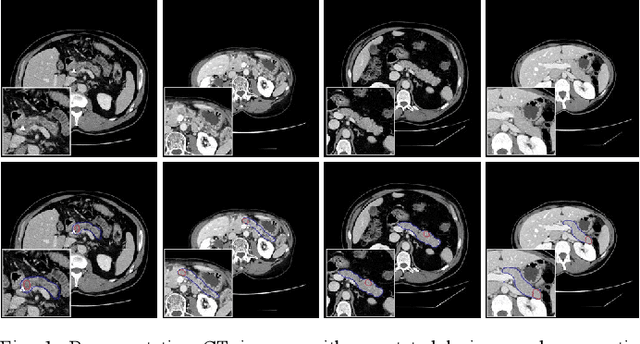

Abstract:Pancreatic cancer, characterized by its notable prevalence and mortality rates, demands accurate lesion delineation for effective diagnosis and therapeutic interventions. The generalizability of extant methods is frequently compromised due to the pronounced variability in imaging and the heterogeneous characteristics of pancreatic lesions, which may mimic normal tissues and exhibit significant inter-patient variability. Thus, we propose a generalization framework that synergizes pixel-level classification and regression tasks, to accurately delineate lesions and improve model stability. This framework not only seeks to align segmentation contours with actual lesions but also uses regression to elucidate spatial relationships between diseased and normal tissues, thereby improving tumor localization and morphological characterization. Enhanced by the reciprocal transformation of task outputs, our approach integrates additional regression supervision within the segmentation context, bolstering the model's generalization ability from a dual-task perspective. Besides, dual self-supervised learning in feature spaces and output spaces augments the model's representational capability and stability across different imaging views. Experiments on 594 samples composed of three datasets with significant imaging differences demonstrate that our generalized pancreas segmentation results comparable to mainstream in-domain validation performance (Dice: 84.07%). More importantly, it successfully improves the results of the highly challenging cross-lesion generalized pancreatic cancer segmentation task by 9.51%. Thus, our model constitutes a resilient and efficient foundational technological support for pancreatic disease management and wider medical applications. The codes will be released at https://github.com/SJTUBME-QianLab/Dual-Task-Seg.